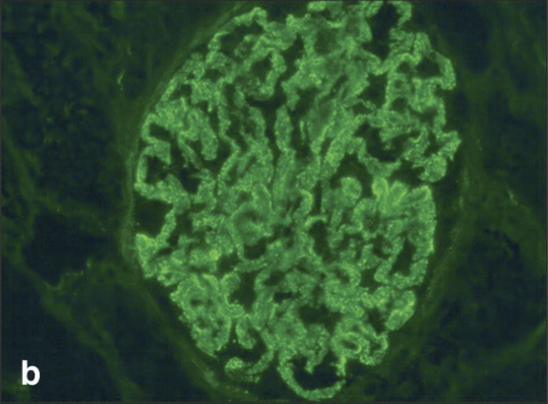

What condition is this

Systemic Lupus erythematosus- green stain